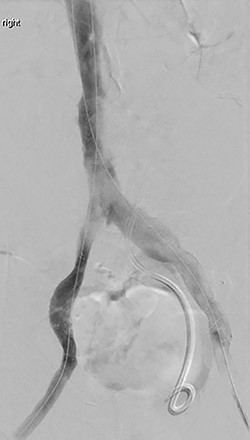

A repeat intravascular ultrasound showed bilateral iliac vein stenosis at the level of the IVC bifurcation. Thus, we deployed 14-mm Wallstents in both iliac veins into the distal IVC. A complete venogram showed adequate flow through the external and common iliac systems bilaterally (Fig. 1). The total operating time was 6 h.

(A) Shows initial retrograde angiogram of right common femoral artery with occlusion at the level of the EIA. (B) demonstrates restoration of flow postangioplasty and stenting.